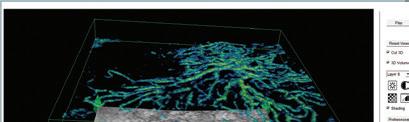

Solix

Nέο Fullrange OCT!

Ανακαλύψτε την επόµενη γενιά OCT Aπεικόνισης από τον Κερατοειδή έως και τον Χοριοειδή!

Ένας µακροχρόνιος ηγέτης µε συνεχείς καινοτοµίες στην τεχνολογία των OCTs, η Optovue παρουσιάζει

το Solix µε νέες δυνατότητες και νέες εφαρµογές που δηµιουργούν απεριόριστες πρακτικές

Συνεχίζει τις καινοτοµίες στην τεχνολογία της OCT Α, αφού προσφέρει την πιο υψηλή ανάλυση (600 Χ 600 Β Scans) σε ελάχιστο χρόνο & στο µεγαλύτερο εύρος λήψης. H νέα πλατφόρµα είναι σχεδιασµένη να δεχτεί και άλλες τεχνολογίες!

Το νέο Solix επιτυγχάνει αγγειογραφία ωχράς και δίσκου σε ακόµα πιο υψηλή ανάλυση µε Ultra High Density σαρώσεις σε καταπληκτικές ταχύτητες στα 120.000 Α-Scans/ second

Γρήγορη και αξιόπιστη OCT Αγγειογραφία, χάρη στις τεχνολογίες αιχµής, διόρθωσης σακκαδικών κινήσεων και 3D PAR 2. Μοναδικό χαρακτηριστκό Wide Field OCT Angio

12mm µε µία λήψη.

Η Optovue, µε το Solix, ενσωµατώνει στο OCT, έγχρωµη κάµερα βυθού, προσφέροντας στο ήδη ευρύ πεδίο δυνατοτήτων της, ακόµη περισσότερες λειτουργίες. ∆ιαθέτει, ανέρυθρη

και έγχρωµη απεικόνιση βυθού, φωτογραφία

οφθαλµικής επιφάνειας και απεικόνιση

µεϊβοµιανών αδένων.

Angioanalytics.

Καινοτοµική λειτουργία µε έγκριση FDA. Μετρήσεις πυκνότητας ροής σε όλες τις στιβάδες, περιφέρειας ενάγγειου ζώνης, εµβαδόν περιοχής ισχαιµίας και πολλές ακόµα σε περιοχή δίσκου και ωχράς.